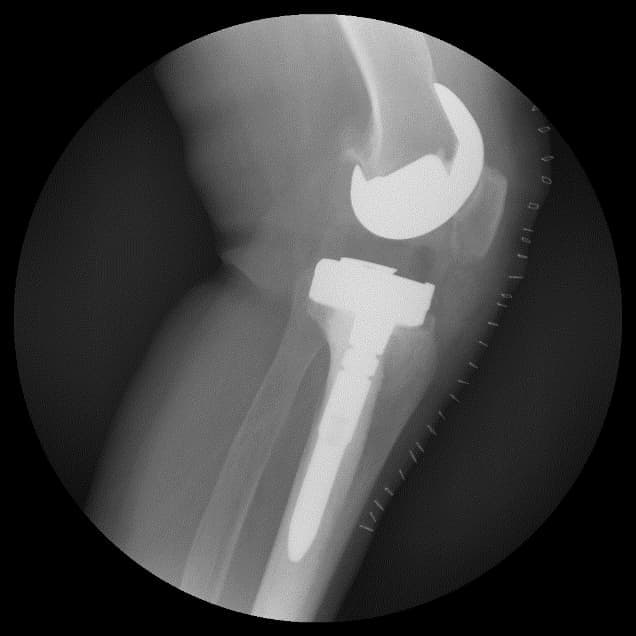

Үе дайрсан ясны анхдагч хавдар, ясны дутмагшлын үед хийгдэх мэс засалimg15Үе дайрсан ясны анхдагч хавдар, ясны дутмагшлын үед хийгдэх мэс засалimg16

Зураг 3. Мэс заслын дараах рентген зураг. Эгц урд, хажуугаас авсан байдал